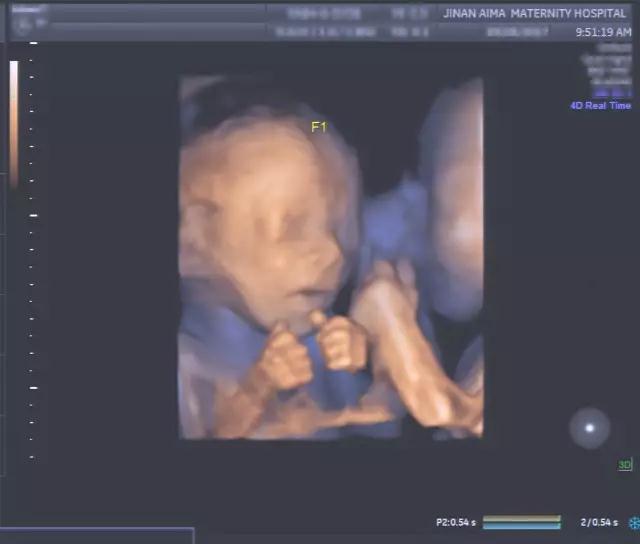

“看到宝宝们在子宫里的亲密举动,这种感觉真是太棒了。”宝妈欣喜地说。

艾玛妇产超声专家朱爱莲表示:“我们经常看到双胞胎宝宝脸部表情的细节,比如微笑和眨眼,还有彼此之间的互动,这是非常有趣、非常温馨的画面。同时,这种亲密的举动能对双胞胎的发育起到帮助作用,而且可能对她们出生后的情感交流有积极的影响。”

不仅如此,四维彩超(四维彩超)更重要的医学意义是通过清晰的画面对胎儿的体表进行检查,及早发现唇裂、脊柱裂,大脑、肾、心脏、骨骼发育不良等各种畸形情况,检测和发现各种异常。简单的说,四维彩超(四维彩超)的作用,就是从零岁起监测宝宝的发育情况,保障每个新生儿的健康!